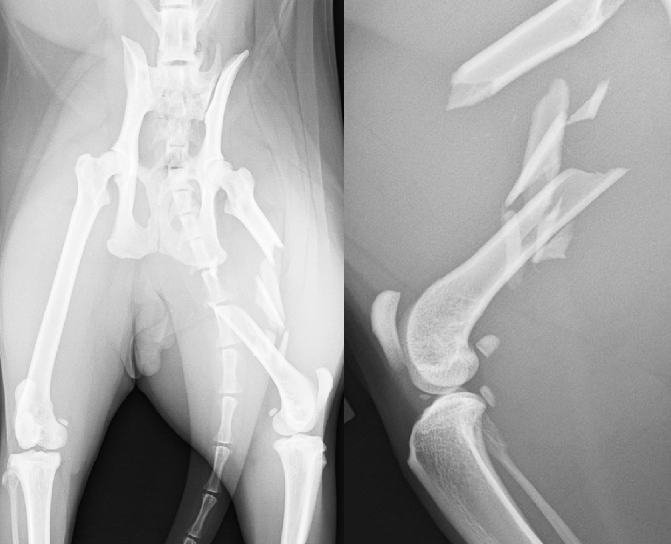

骨折

小型犬の前肢骨折(橈尺骨骨折)は転倒や落下で簡単に骨折します。

ほとんどがプレートとスクリュー固定にて完治できますからできるだけ早期に手術を行います。

後肢の骨折(骨盤、大腿骨、脛骨)は高エネルギー外傷(交通事故、高い所からの落下など)で全身にダメージを受けている場合があります。

必ず全身状態の評価を行ったうえで整復固定手術を行います。

【術前】橈尺骨遠位端プレート整復固定 -

【術後】橈尺骨遠位端プレート整復固